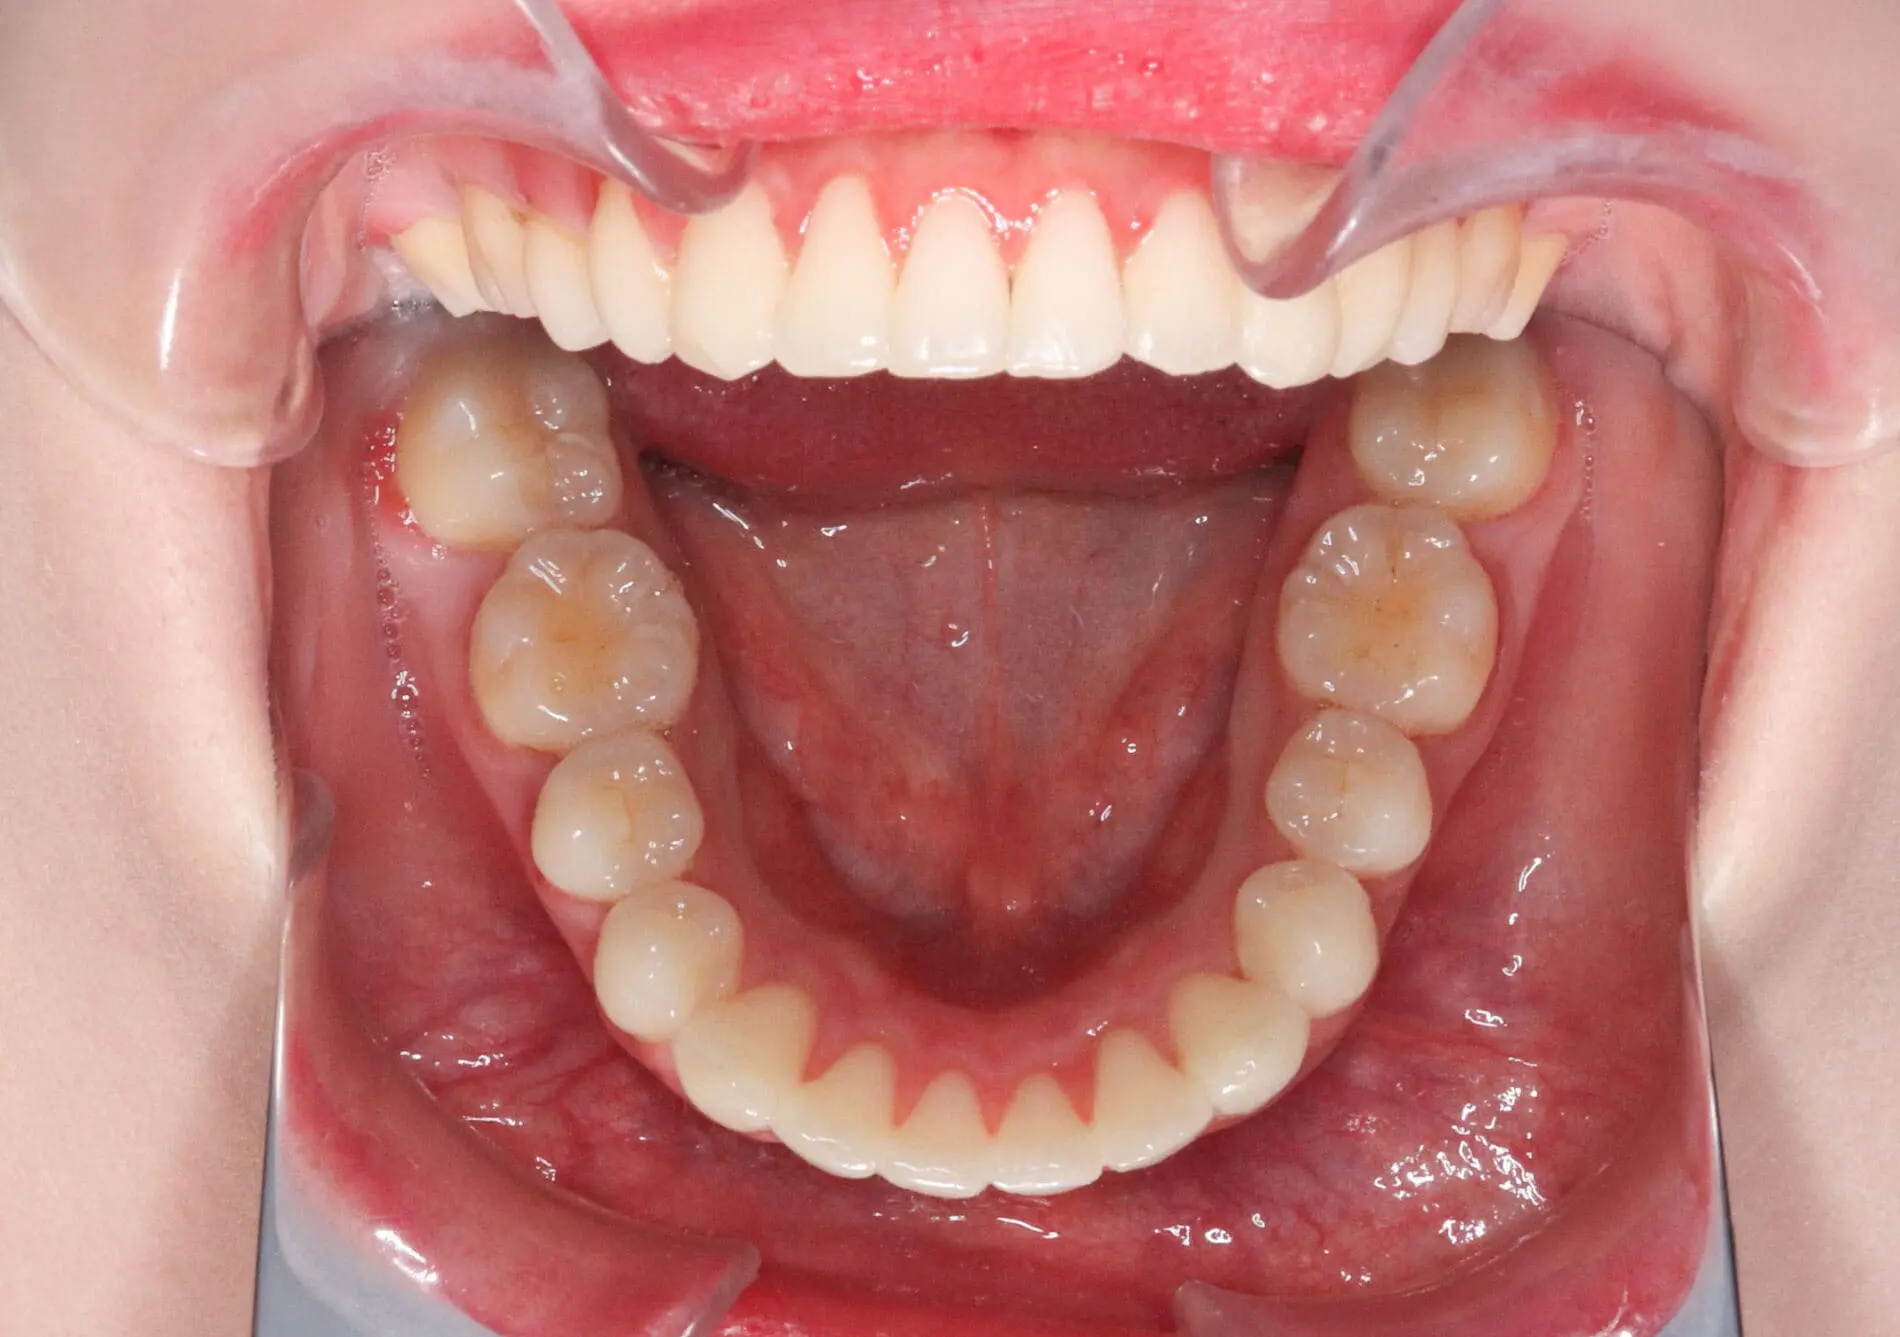

Amazing Braces Before and After Photos in Kirkland, WA

Crowding